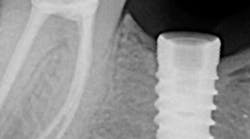

• Nobel Biocare will establish the Foundation for Oral Rehabilitation (FOR) as a scholar-led, international initiative to promote oral health care and humanitarian leadership • Upcoming NobelProcera® 2G Scanner with direct access to unrivaled prosthetic solutions • New partnership with 3Shape™ will offer open access to NobelProcera® Abutments • Latest features reaffirm NobelClinician™ Software is the key to successful implant treatments • New NobelReplace® Conical Connection and Replace Select™ implants increase treatment flexibility • Innovative new features added to the iPad®-operated OsseoCare™ Pro drill motor • New options for NobelProcera® Abutments on Biomet 3i™, Camlog® and Zimmer® implant platforms • More restorative flexibility with NobelProcera® Implant Bars on Straumann® implant platforms • Immediately loaded NobelActive® implants display a high cumulative survival rate in recent study Nobel Biocare proudly takes its place at one of the largest dental gatherings in the world, the 35th International Dental Show in Cologne, Germany, March 12-16. The popularity and tradition behind this event makes it a prime opportunity to announce the endowment of FOR, the Foundation for Oral Rehabilitation. FOR, which will be led by the most renowned scholars in oral rehabilitation, will be a landmark in Nobel Biocare's history and commitment to training, education, science and humanitarian engagement. Additionally at IDS, Nobel Biocare is announcing exciting upcoming CAD/CAM developments to NobelProcera including a new second-generation scanner and open access partnership with 3Shape.RELATED |Large clinical study of dental implants yields impressive 10-year outcomesRELATED |Case example of an anterior esthetic implant restoration with good surgical-restorative communications Nobel Biocare is a focused and specialized leader in implant-based dental restorations – including implant systems, high-precision individualized prosthetics, CAD/CAM, diagnostics, treatment planning, and guided surgery – that provides support to customers throughout their professional and practice development. Nobel Biocare offers comprehensive education programs to support the development of dental professionals to help them become more efficient and effective in their work. The sponsorship of the new Foundation for Oral Rehabilitation is an extension of this strong emphasis on training and education and underscores the future contributions Nobel Biocare plans to make to the oral health community. Nobel Biocare is a CAD/CAM pioneer as the first to offer fully-automated industrial CAD/CAM dental prosthetic production. The NobelProcera CAD/CAM system is a leader in innovative technology, materials, and products delivering ready-to-use restorations with outstanding quality. The announcements of a new NobelProcera 2G Scanner and an open access partnership with 3Shape for NobelProcera Abutments, both to be launched later this year, offer even more access to superior products and solutions that help dental professionals treat more patients better. The patient is at the forefront of Nobel Biocare’s mission, “Designing for Life,” an ambition to improve every patient’s quality of life with superior products and solutions designed to give functional and natural-looking tooth restorations that aspire to last a lifetime. For each core step of the patient treatment workflow – diagnostics and treatment planning, surgery, prosthetic restoration and post-treatment care – Nobel Biocare provides superior products and solutions to ensure maximum treatment safety, patient comfort, and long-term success. At Nobel Biocare, product innovation is again taking the lead and driving the organization to fulfill its mission. Additionally, there is also the firm belief that continuing education and training on its superior products and solutions are not only key to a dental professional's success, but are essential to enhancing a patient's experience, treatment outcome, and ultimately, quality of life.Nobel Biocare will establish the Foundation for Oral Rehabilitation (FOR) as a scholar-led, international initiative to promote oral healthcare and humanitarian leadership The Foundation for Oral Rehabilitation builds on Nobel Biocare’s strong history and commitment to science and education. “Our mission is to achieve effective worldwide patient care through scholarship and humanitarian engagement,” according to George Zarb, who will be the chairman of the foundation. The official inauguration of FOR will take place at the Nobel Biocare Global Symposium in New York, June 20-23. FOR will be organized into three sections: FOR Education, FOR Science, and FOR Humanity and will be led by a board of trustees consisting of world-renowned clinicians and scholars.Upcoming NobelProcera® 2G Scanner with direct access to unrivaled prosthetic solutions The upcoming second-generation NobelProcera 2G Scanner builds on the more than 25 years of CAD/CAM experience behind all NobelProcera solutions and tops its predecessor which has already proven to be an extremely accurate scanner on the dental market. [1] The new scanner has a similar look to the original with exciting new elements including advanced automation features which are designed to increase productivity. Existing users of the NobelProcera Scanner will be able to upgrade their current scanner to the new 2G version which will be available later this year.New partnership with 3Shape™ will offer open access to NobelProcera® Abutments Later this year, users of the 3Shape Dental System will be able to integrate their system to gain access to the unrivaled quality of NobelProcera Abutments in zirconia and titanium for both Nobel Biocare and other major implant systems. After integrating with NobelProcera, 3Shape users simply maintain their current workflow of scanning and designing using the 3Shape Dental System to access the extensive global production network of NobelProcera. Interested 3Shape users should contact Nobel Biocare to obtain the required interface file. Availability may depend on the version in use and which 3Shape Partner has provided the Dental System.Latest features reaffirm NobelClinician™ Software is the key to successful implant treatments NobelClinician provides precise implant planning options for predictable outcomes and is a very effective visual communication tool. As the first diagnostics and treatment planning software available for both Mac OS® X and Windows®, NobelClinician serves an increasing demand in the dental community as dental professionals frequently also use Apple® devices in their dental practices. The latest version of NobelClinician Software significantly enhances diagnostic capabilities through a new 3D rendering technology called volume rendering. Clinicians can now instantly see below the surface of 3D bone models from (CB)CT patient scans and immediately identify and further inspect internal anatomical structures like tooth roots or previously planned implants while treatment planning. Dental professionals can now also use NobelClinician to import 2D images – like existing pre- and postoperative dental X-rays or clinical patient pictures (e.g. patient’s smile, intraoral clinical images, etc.) – and visualize them next to the 3D view. This allows the dental professional to be even closer to the real situation while virtually planning or discussing in an interdisciplinary treatment team and also considering availability of bone and prosthetic needs. All new views and pictures are fully integrated into the clinical report. Treatment scenarios can be shared securely and hassle-free through the NobelConnect collaboration feature to align computers within the practice or with other treating team members at different geographical locations. The new and innovative NobelClinician Communicator iPad® app gives dental professionals a convenient platform to present and effectively communicate NobelClinician treatment plans to their patients. This revolutionary iPad® app can be used in a comfortable setting to easily display selected clinical pictures, X-rays and the patient’s 2D or 3D images for helping them to understand their treatment plan. The dental professional can use any iPad® with the NobelClinician Communicator app to open their NobelClinician patient presentations by just logging in with a NobelClinician user account. Additionally, the patient can confirm having seen and studied the information on the treatment flow by signing off on the iPad® presentation. The patient’s iPad® presentation is securely stored on the online NobelConnect space ensuring no information will be lost.New NobelReplace® Conical Connection and Replace Select™ implants increase treatment flexibility The line extension of partially machined collar implants featuring the new NobelReplace Conical Connection PMC and Replace Select Tapered PMC ensures that the original tapered implant system provides total patient treatment flexibility. No matter the patient requirements or clinician preference, NobelReplace and Replace Select represent one system for all clinical needs. The new NobelReplace Conical Connection PMC adds an additional option to the original with a 0.75 mm machined collar. NobelReplace Conical Connection combines the original tapered implant body with a sealed conical connection to offer dental professionals an esthetic solution for all indications. The body of all NobelReplace and Replace Select implants mimics the shape of a natural tooth root and is designed for high initial stability in all loading protocols including Immediate Function. Replace Select Tapered – the safe, reliable and easy-to-use implant with the internal tri-channel connection – now offers two collar options for different clinical needs and treatment preferences. The original Replace Select Tapered has been available with a 1.5 mm machined collar for tissue-level restorations and the new Replace Select Tapered PMC is available with a 0.75 mm machined collar. The micro-roughness of the machined collar and abutment surface are similar to natural tooth enamel (Ra 0.3–0.5). These harmonious surface conditions promote optimal soft tissue attachment and a seal by the junctional epithelium for healthy and highly esthetic results.Innovative new features added to the iPad®-operated OsseoCare™ Pro drill motor The iPad®-operated OsseoCare Pro drill motor has added some new and innovative features to the latest application update now available in the Apple® App Store. New customizable drilling protocols allow users to create and save their own drilling protocols by changing or adding steps – both for Nobel Biocare and other implant systems. Additionally, OsseoCare Pro users can now use their handpiece of choice as well as switching between different contra-angles and handpiece ratios during surgery. Also, a new note-taking feature allows users to keep a more effective overview of surgery with the ability to add notes before, during and after surgery which can also be included in the reporting feature. The intuitive user interface of the OsseoCare Pro combined with unique handling features provides clinicians and their patients with high treatment efficiency and security. Available free of charge from the Apple® App Store, the OsseoCare Pro application delivers highly user-friendly operations and opens up numerous avenues in terms of customization options.New options for NobelProcera® Abutments on Biomet 3i™, Camlog® and Zimmer® implant platforms The latest additions to the assortment of third-party NobelProcera Abutments provides affordable and high-quality options that pair patient needs with individual products. In addition to the existing third-party NobelProcera Abutments for Straumann, Astra Tech and Thommen – a whole new range of NobelProcera Abutments on Biomet 3i, Camlog and Zimmer implant platforms are now available. All NobelProcera Abutments are meticulously developed, verified, and validated to meet engineering requirements and user needs.More restorative flexibility with NobelProcera® Implant Bars on Straumann® implant platforms NobelProcera users can gain a significant competitive edge in expanding their business with the new in-lab scanning of NobelProcera Implant Bar Overdenture for Straumann implant platforms. NobelProcera Implant Bars for Straumann Standard/Standard Plus and Bone Level allow for even more restorative flexibility with precision engineering that supports basic to advanced cases. The extensive experience in high-end industrial manufacturing available with the global production network of NobelProcera, allows dental professionals to take advantage of a whole new range of implant restorative options for addressing patient needs. The NobelProcera Implant Bar Overdenture for Straumann implant platforms has been tested with a new 3D fit assessment to verify the high precision of fit of NobelProcera Implant Bars on Straumann implant platforms. The method is used to confirm precision of fit in order to reduce mechanical complications and ensure longevity which is particularly relevant when developing CAD/CAM-generated dental implant substructures.[2]Immediately loaded NobelActive® implants display a high cumulative survival rate in recent study Since its launch five years ago, NobelActive has attracted new users at a pace the dental industry has not seen before – recently passing 1,000,000 NobelActive implants placed in patients worldwide. The most recent addition, NobelActive 3.0, provides narrow-fitting implant solutions and is specifically designed for the replacement of single-unit maxillary lateral incisors as well as mandibular lateral and central incisors. A new clinical study with three years of follow-up data confirms the exceptional performance of NobelActive. The study recently published in the European Journal of Oral Implantology entitled, "Comparison of variable-thread tapered implant designs to a standard tapered implant design after immediate loading. A three-year multi-centre randomised controlled trial" aimed to verify whether immediate loading could be applied with NobelActive while achieving the same stable marginal bone levels and soft tissue healing as with the well-documented NobelReplace Tapered implant. After three years, the cumulative survival rate was 96% to 97%. Marginal bone levels were measured on intraoral radiographs and, after initial bone remodeling, demonstrated stable or improving levels during the second and third year. The mean papilla score increased significantly in all treatment groups.[3] Visit the Nobel Biocare booth at IDS in Hall 4.1, location A90-91, for more details and to experience the latest innovations in implant-based dentistry. For more information, visit http://www.nobelbiocare.com. Nobel Biocare (NOBN, SIX Swiss Exchange) is a world leader in innovative restorative and esthetic dental solutions. As a complete solutions provider, Nobel Biocare offers the most comprehensive range of solutions from tooth to root, for single tooth to fully edentulous indications. The solutions portfolio covers dental implants (including the key brands NobelActive®, Brånemark System® and NobelReplace®, individualized prosthetics and equipment (NobelProcera®, guided surgery solutions and biomaterials). Nobel Biocare has approximately 2’500 employees and recorded revenue of EUR 580.5 million in 2012. The company is headquartered in Zurich, Switzerland. Production takes place at seven sites located in Canada, Israel, Japan, Sweden, and the U.S. Nobel Biocare has 34 direct sales organizations.References 1. Holst S, Persson A, Wichmann M, Karl M. Digitizing implant position locators on master casts: comparison of a noncontact scanner and a contact-probe scanner. Int J Oral Maxillofac Implants. 2012 Jan-Feb;27(1):29-35. 2. Holst S. Tawdrous RE, Karl M. "Description of a Novel Technique for Three-Dimensional Fit Assessment of Dental Restorations." IFMBE Proceedings Volume 31, 2010, 6th World Congress of Biomechanics (WCB 2010). Editor Chwee Teck Lim. India: Springer, 2010. 1479-1482. (Print). 3. Arnhart C, Kielbassa AM, Martinez-de Fuentes R, Goldstein M, Jackowski J, Lorenzoni M, Maiorana C, Mericske-Stern R, Pozzi A, Rompen E, Sanz M, Strub JR. Comparison of variable thread tapered implant designs to a standard tapered implant design after immediate loading. A three-year multicenter randomised controlled trial. Eur J Oral Implantol. 2012;5:123-136.